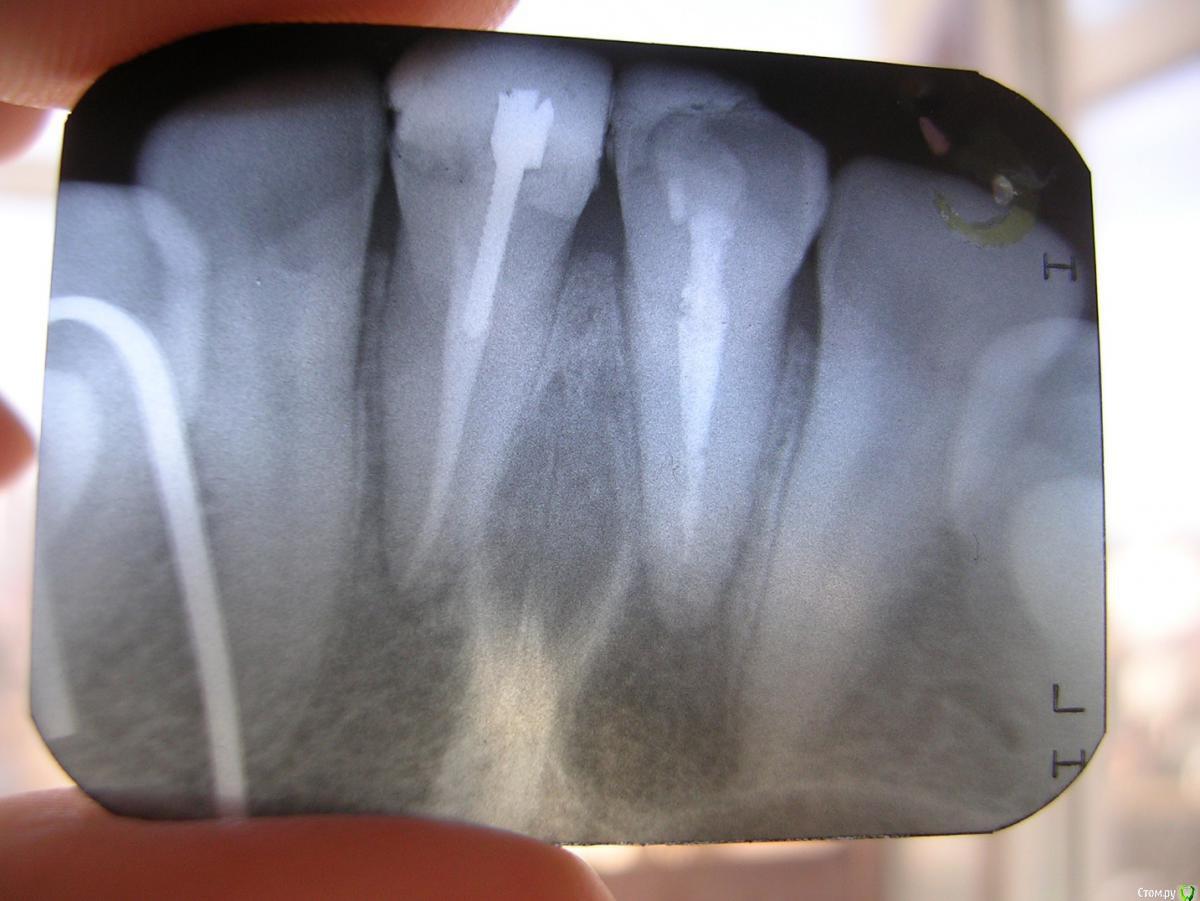

vlazub Опубликовано 1 февраля, 2019 Поделиться Опубликовано 1 февраля, 2019 Уважаемые доктора! В 2006 году анкером заделали скол зуба, в 2016 воспаление-сделали надрез десны для отвода флюса -далее в 2016 лечение канала под микроскопом, в 2019 повторное воспаление, есть ли возможность спасти 21 зуб(с маленьким сколом) и каким способом? Сильно ли увеличилась так называемая киста? Интересны специалисты в Москве(терапевт или уже хирург)! Буду благодарен за любые советы!3ф-1февр19.bmp Ссылка на комментарий

vlazub Опубликовано 1 февраля, 2019 Автор Поделиться Опубликовано 1 февраля, 2019 рентген-снимок на настоящий момент Ссылка на комментарий

vlazub Опубликовано 2 февраля, 2019 Автор Поделиться Опубликовано 2 февраля, 2019 11 пока не беспокоил там сразу убили нерв и реставрировали, а вот 21 пролечили под микроскопом в 2016(но при нажимании с того времени на десну по настоящее время сохранялись болевые ощущения) - сейчас опять разболелась десна - сделали разрез и говорят сильно увеличилась киста. Непонятно: удалять кисту без вырывания зуба, вырывать зуб или еще раз попробовать пролечить под микроскопом? Ссылка на комментарий